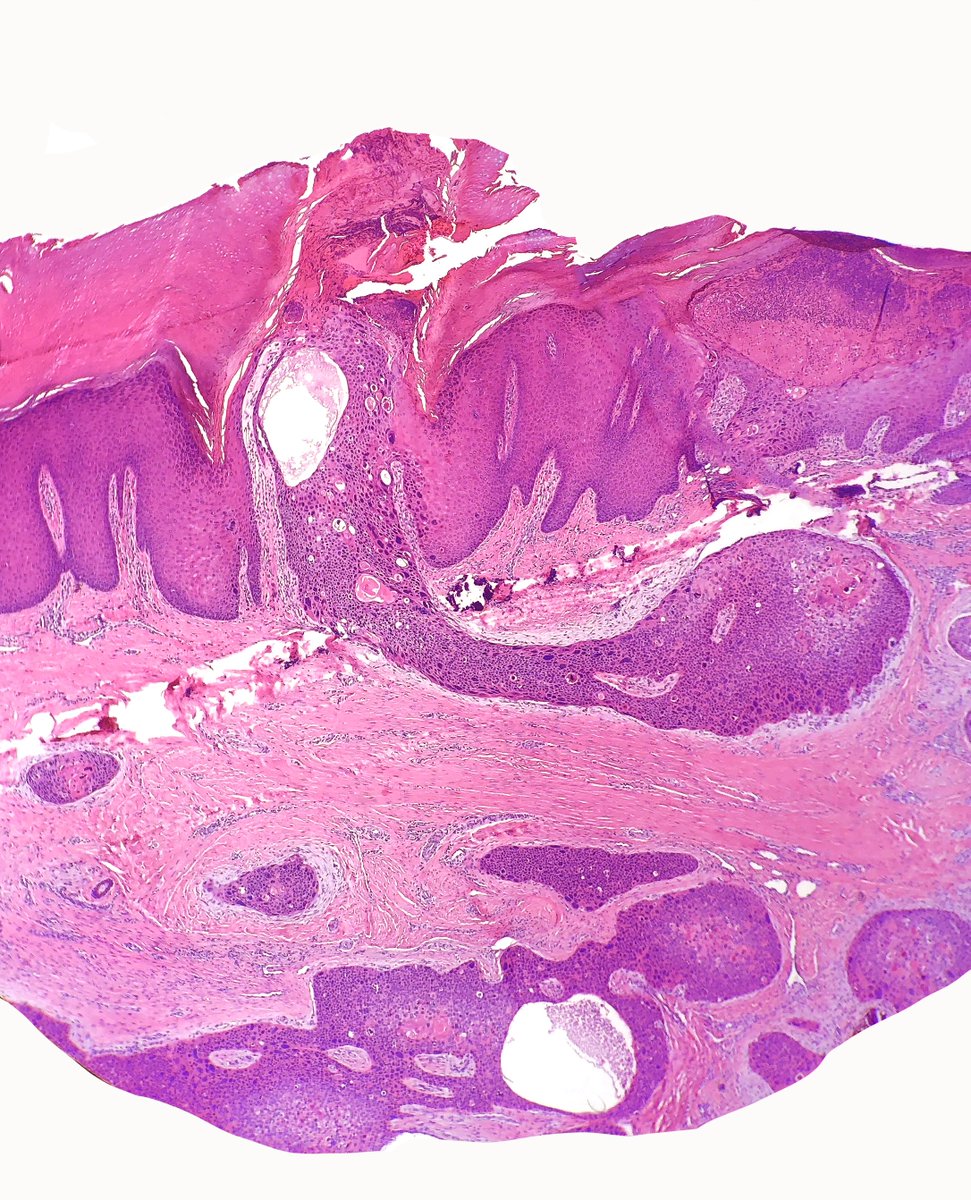

Elderly man, foot mass. Previous superficial shave biopsy called SCCIS. This is the excision. #dermpath